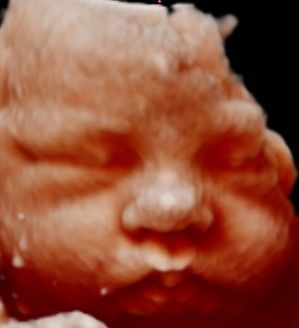

Ecografía 4D / 5D